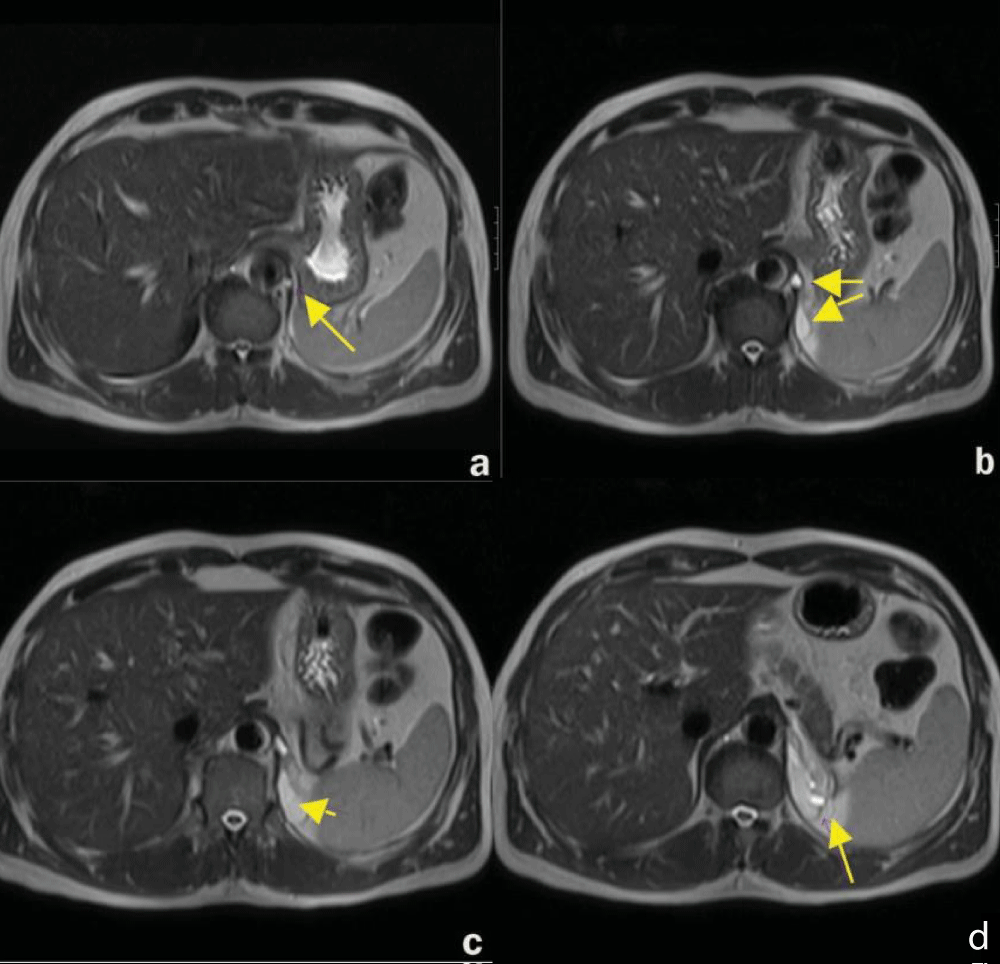

MRI is usually performed after an initial CT scan to provide additional details about the cyst and its surrounding structures. The retroperitoneal bronchogenic cyst has variable signal intensity on MRI (Figure 3). Simple cysts will typically display a very low signal intensity on T1-weighted imaging. Higher signal intensities may be seen because of paramagnetic entities including protein or methemoglobin resulting from hemorrhage which can be suspended in the cystic fluid. The retroperitoneal bronchogenic cyst will typically produce variable intermediate-to-high signal intensity lesions on T1-weighted images. However, based on the contents of the retroperitoneal bronchogenic cyst, it may mimic a solid mass on CT and T1-weighted MRI imaging. As a result, T2-weighted MRI imaging is required, generating an extremely high signal intensity. It is also noteworthy that retroperitoneal bronchogenic cysts can be used to distinguish retroperitoneal bronchogenic cysts from teratoma based on their lack of signal intensity inversion on T1-weighted fat-suppressed imaging [1-3,5].

Download Image

Figure 3: Magnetic Resonance imaging of the abdomen in axial plane (a-d) showing a retroperitoneal bronchogenic cyst [5].